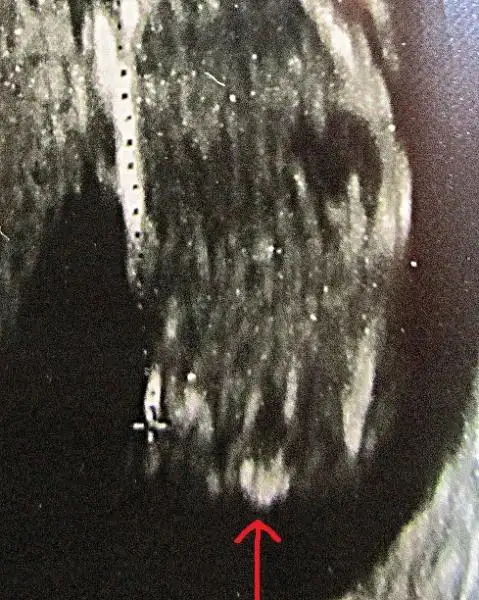

cnm benm resmimede bi yorum yapar mısın shzofren arkadaşım göremedi arkasını dönmüş dedi ama doktor ultrasonu bana çevirdiğinde nubunu gördüm ben açık seçik yukarı bakıyordu bide sen bi bak canm nub görünüyor mu doktor inatla 20 haftadan önce söylemem dedi cinsiyetini:44: $IMG_20130905_120503.webp

cnm benm resmimede bi yorum yapar mısın shzofren arkadaşım göremedi arkasını dönmüş dedi ama doktor ultrasonu bana çevirdiğinde nubunu gördüm ben açık seçik yukarı bakıyordu bide sen bi bak canm nub görünüyor mu doktor inatla 20 haftadan önce söylemem dedi cinsiyetini:44:Eki Görüntüle 797104

kizlar inanin net birsey gorunmuyor uzgunummmm:50: